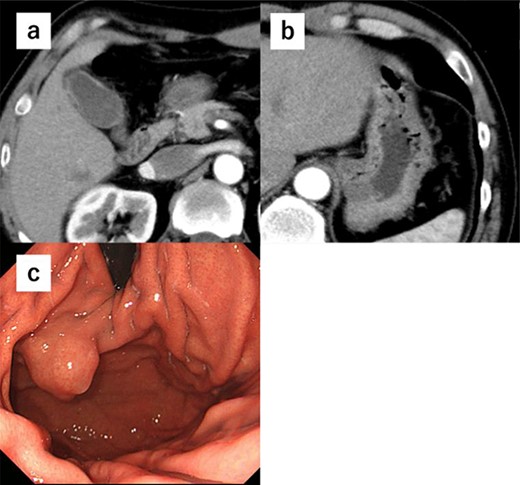

A 52-year-old man was diagnosed with acute cholecystitis after presenting to the emergency department of our hospital with right upper quadrant abdominal pain. Blood tests revealed the following measurements: white blood cell count, 15 300/mm3; C-reactive protein, 0.03 mg/dL; total bilirubin, 1.2 mg/dL; direct bilirubin, 0.7 mg/dL; alkaline phosphatase, 338 U/L; aspartate transaminase, 126 U/L and alanine aminotransferase, 66 U/L. The abovementioned values revealed an inflammatory reaction and mild elevation of hepatobiliary enzymes. CT revealed cholecystitis, and a submucosal tumor measuring 3.5 cm in diameter was incidentally detected (Fig. 4a and b). The patient was treated with antibiotics for cholecystitis and referred to our department for simultaneous surgery. Upper endoscopy revealed a tumor in the anterior wall of the gastric cardia near the EGJ (Fig. 4c). He underwent robot-assisted laparoscopic resection for the tumor, combined with endoscopy and robot-assisted cholecystectomy (Fig. 5a–c). The port positions were the same as those in Case 1. The operative time was 228 min, and blood loss was 1 mL. No adverse postoperative events occurred, and the patient was discharged on postoperative day 7.

(a) We performed robot-assisted cholecystectomy. (b) The tumor location was confirmed endoscopically, and the tumor was resected minimally. (c) Reconstruction was performed by Albert–Lembert suture.